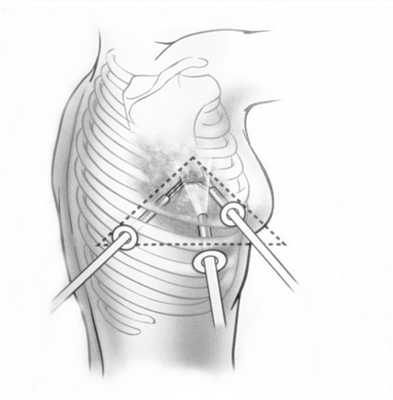

При невозможности получить образец ткани для исследования эндоскопически применяются инвазивные методы: трансторакальная биопсия, медиастиноскопия, видеоторакосокпия. Последние два метода — это серьезные операции, которые проводятся в специализированных медицинских учреждениях.

- Эндоскопическая диагностика. При опухолях средостения используются бронхоскопия, медиастиноскопия, видеоторакоскопия. При проведении бронхоскопии исключается бронхогенная локализация опухолей и прорастание опухолью средостения трахеи и крупных бронхов.

- Пункционная биопсия. Также в процессе исследований возможно выполнение транстрахеальной или трансбронхиальной биопсии опухоли средостения. В ряде случаев взятие образцов патологической ткани осуществляется посредством трансторакальной аспирационной или пункционной биопсии, проводимой под ультразвуковым или рентгенологическим контролем. При подозрении на лимфоидные опухоли средостения выполняется костномозговая пункция с исследованием миелограммы.

- Хирургическая биопсия. Предпочтительными способами получения материала для морфологического исследования являются медиастиноскопия и диагностическая торакоскопия, позволяющие осуществить биопсию под контролем зрения. В некоторых случаях возникает необходимость в проведении парастернальной торакотомии (медиастинотомии) для ревизии и биопсии средостения. При наличии увеличенных лимфоузлов в надключичной области проводят прескаленную биопсию.